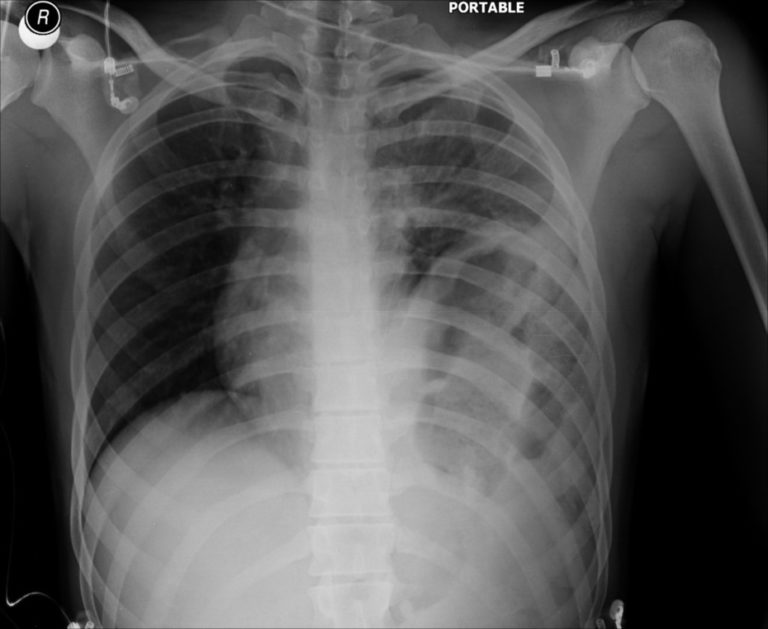

Traumatic Diaphragmatic Rupture. CXR Annotated. JETem 2019 JETem Diaphragm Rupture Radiology Diaphragm and diaphragmatic injuries with kylee brooks md, parker hambright md, alexis holland md, and. Acute displaced fractures of the right anterolateral third through eighth ribs. Although the diagnosis may be obvious at standard chest. Blunt trauma produces larger, radial. Specific diagnostic findings of diaphragmatic rupture on chest radiographs may not be seen in up to 50% of. Large defect. Diaphragm Rupture Radiology.

From jetem.org